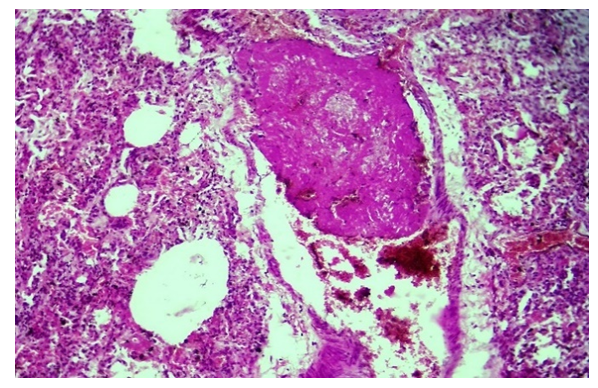

COVID-19 infection is an acute infection caused by a coronavirus, the causative agent of which is the SARS-CoV-2 ACE2 enzyme, which has a cytotoxic effect on all existing cells, including most cells of the lung tissue. The abundance of the ACE2 enzyme in the endothelium of pulmonary blood vessels continues with the development of a strong and scattered discirculation process, which continues with their extensive damage, endotheliosis, endotheliitis, coagulopathy, the formation of blood clots, vasculitis, microvasculitis. Coagulopathy in the form of microangiopathy and microthrombi leads to bleeding from almost all blood vessels and develops diffuse hemorrhagic inflammation in lung tissue. When the lungs of those who died from the infection of COVID-19 were studied morphologically, the following changes were found. It is determined that all the blood vessels of the lungs, including pulmonary artery branches, bronchial artery branches, and pulmonary vein branches, are almost equally expanded, filled with blood, blood is poured around the small blood vessels, and the wall of the alveolar space is thickened due to scattered and diffuse hemorrhage. When studied under the microscope lens, it is observed that all the capillaries in the wall of the alveolar space have expanded sharply, almost all of them have been surrounded by diapedesis (Fig. 1). | Figure 1. The capillaries of the alveolar walls are full, blood is poured around them. Stain: H-E. size: 10x40 |